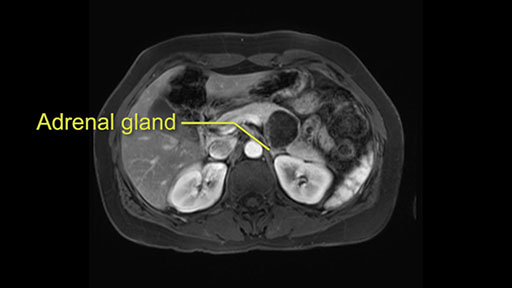

Tumor proximity to left adrenal gland

The lesion also is quite posterior. While the plane between the cyst and the left adrenal gland is often preserved, we do have to pay attention here so that we remain in the right plane and maintain our margin here. Occasionally in these cases, en bloc adrenalectomy needs to be performed.

Sometimes with even benign lesions of the spleen you can have quite a lot of inflammation in the retroperitoneum and so I do think about and wonder whether I will have some difficulty in the retroperitoneum and I usually look at the scan for that purpose. It looks like there is no inflammation in the retroperitoneum. It does look very close to the patient’s left adrenal gland but knowing the planes and suspecting that there isn’t any active inflammation, this should be able to come off the left adrenal gland without any difficulty. But obviously prepared to take some of the left adrenal if that’s necessary in this procedure. So those are my procedure-specific slowing down moments in a distal pancreatectomy when I’m considering a laparoscopic approach. I think the patient-specific slowing down moments in this particular case I have discussed with the procedure-specific moments. I don’t really see any other issue or that I have to be careful of or consider.